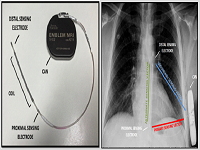

Subcutaneos Implantable Cardioverter: Defibrillator: Is the Conventional Pre-Implant Screening Enough to Assess Eligibility?

Victoria Galizia Brito, Teresa Falcó Martinez, Aina Bibiloni Cladera, Diego Lozano Medina, Vicente Peral Disdier, María del Carmen Expósito Pineda, Carlos Grande Morales

International Journal of Innovative Research in Medical Science·January 1, 2023